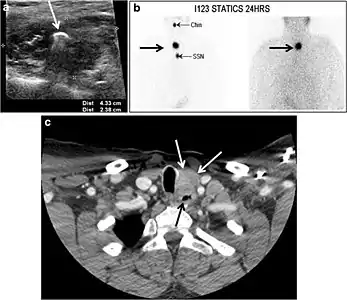

Fig. 9. A 58-year-old male patient with persistence PTC at thyroid bed with hypervascular nodal metastasis. a–c Transverse greyscale and colour Doppler neck ultrasound demonstrate hypoehoic soft tissue in the left thyroid bed (white arrow in a). There are a heterogeneous enlarged lymph nodes at level 2 and 3 with markedly increased vascularity (white arrow in b and c). d–f Enhanced axial CT images of the neck demonstrate a 2.7 × 1.4 cm hypodense soft tissue lesion anterior to the left carotid sheath (white arrow). There are left-sided enhancing abnormal and enlarged lymph nodes at cervical level 2 and 3 (black arrows).[1]